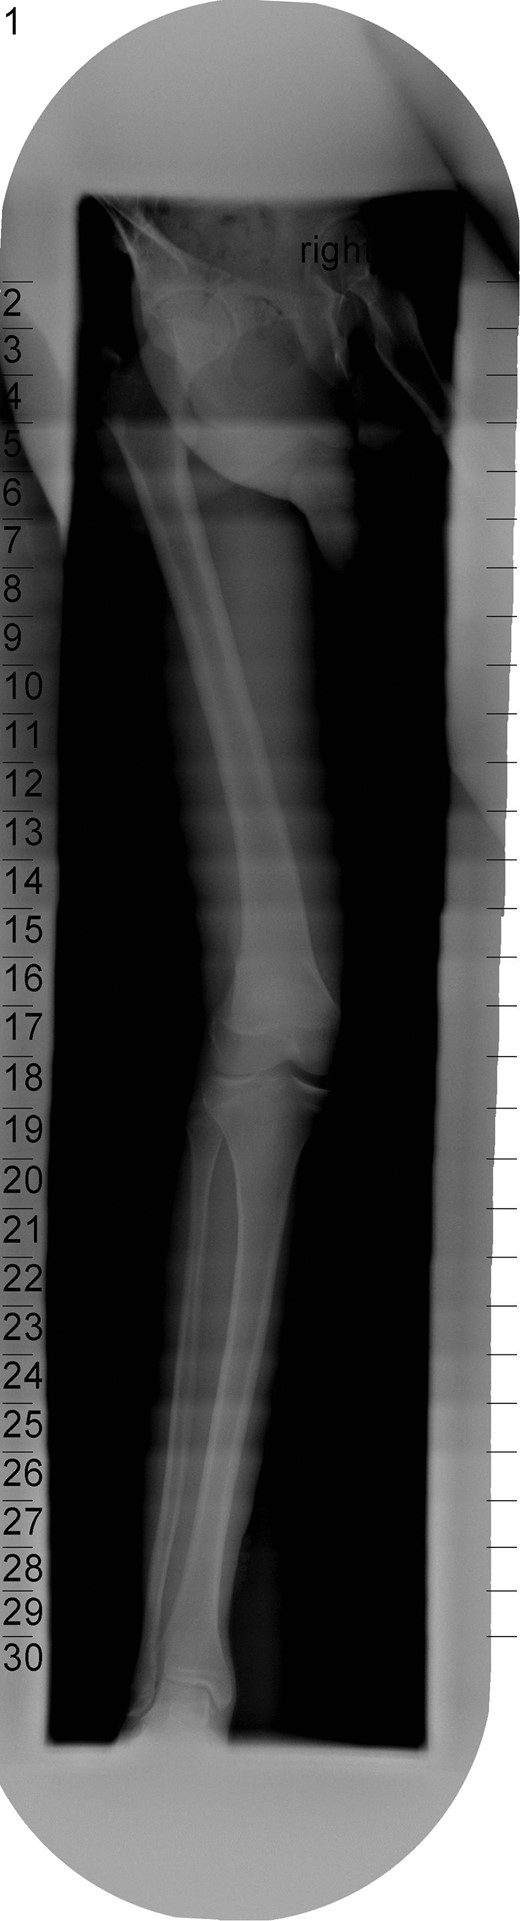

The patient's initial management was non-operative with a period of knee protection with a range of movement brace and intensive rehabilitation. Approximately 3 months after the index injury he returned to competitive football but shortly after his return sustained a further valgus injury and despite further conservative treatment was unable to return to sport. He was referred to our service with ongoing instability symptoms. Upon clinical assessment we noted an asymmetric valgus alignment of the knee and abnormal laxity of the MCL. Radiographic investigations revealed an abnormality of the lateral distal femur and alignment radiographs confirmed the valgus mal-alignment with abnormal opening of the medial tibio-femoral joint space on single-leg stance radiographs (Figs 2–4). We obtained the patient's MRI scan and reviewing this with Radiology colleagues revealed subtle changes of increased lateral femoral physis fluid density on T-2 weighted images consistent with a Salter Harris Type V injury (Fig. 5).

Long-leg alignment radiograph showing valgus deformity of the right knee.